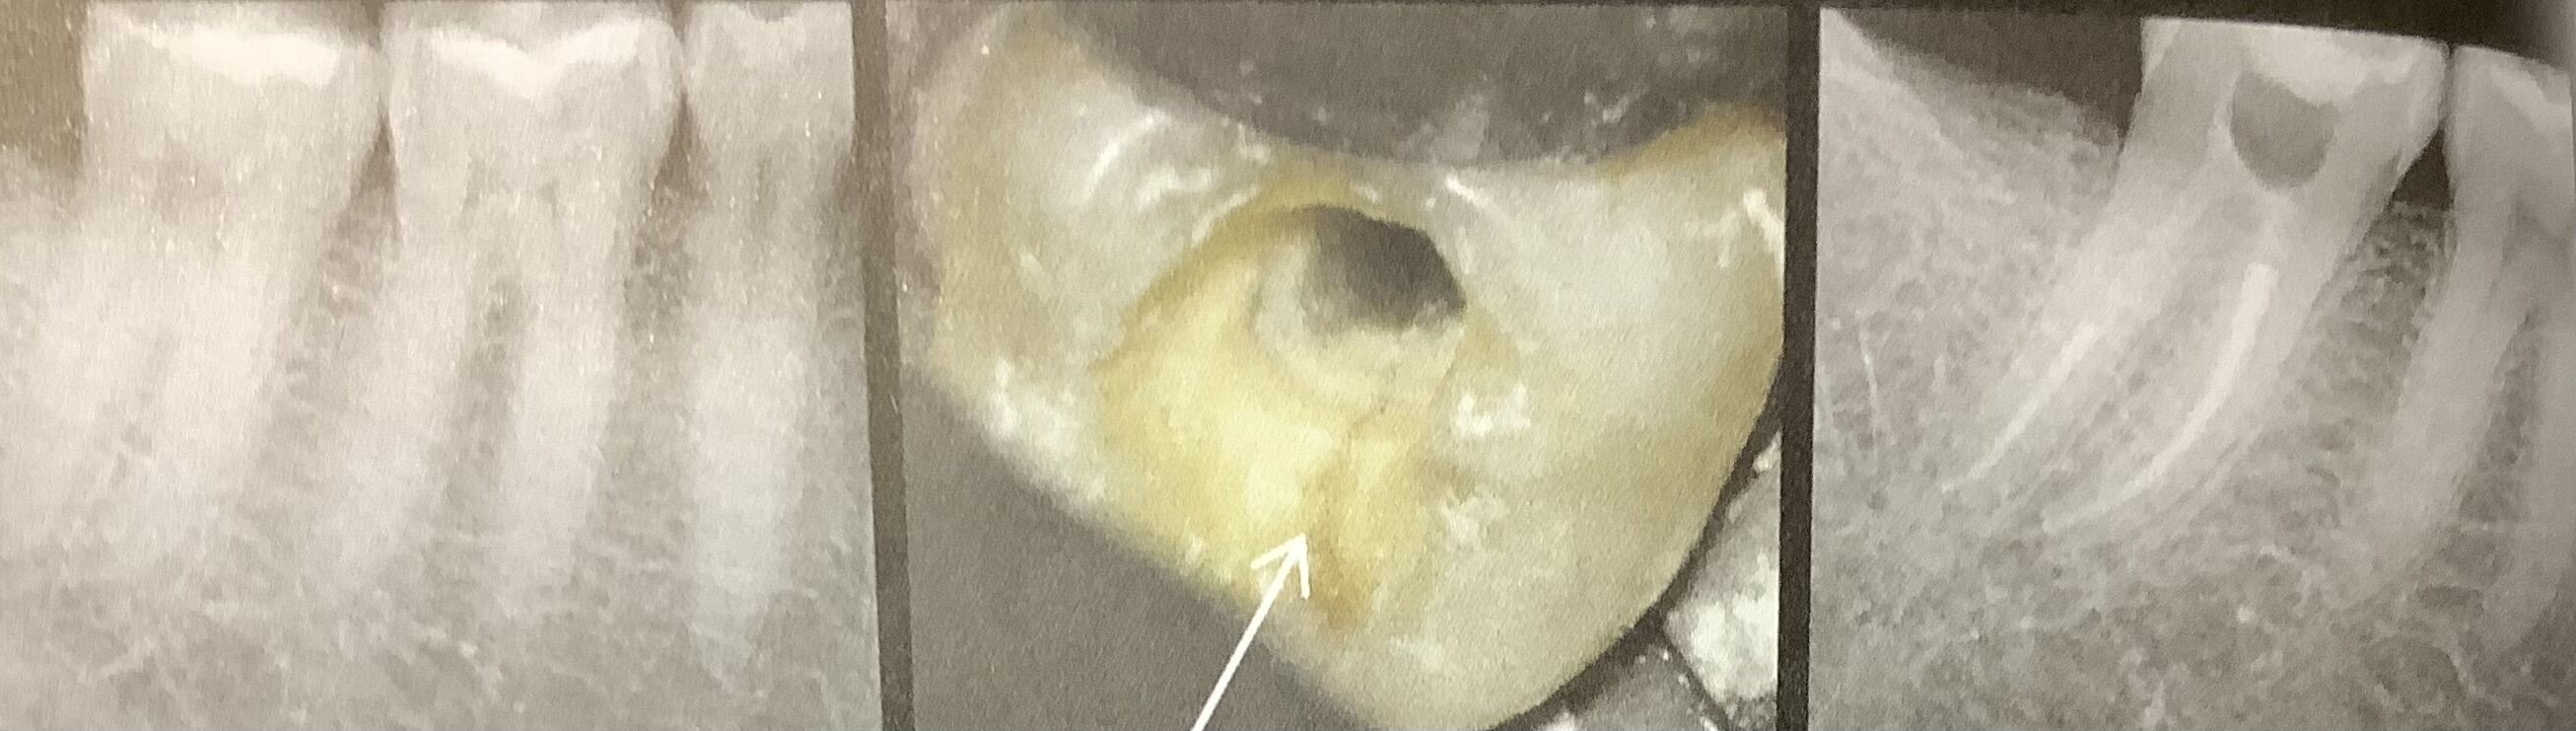

歯のヒビ その9

根っ子にまで進んだヒビの治療方法は?

⚪︎顕微鏡で見て、歯の中からヒビの広がりを調べてくっ付ける。出来ればヒビの下まで。

⚪︎噛み合わせを低くしておいて、そっち側で咬まないように伝えます。

⚪︎出来るだけ早くに被せて、噛み合わせが強くなり過ぎないように注意。

⚪︎定期的に噛み合わせをチェックする。